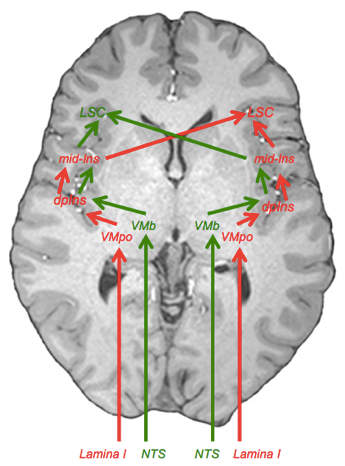

vad händer när vi går ifrån VMpo tll insula kopplat till interoception?

Ifrån VMpo går singaler till dorsla posterioa insula (även känd som Interoceptiva kortex).

- Vekar likt S1 och gör så vi kan känna av var ifrån smärtan kommer ifrån

- Obs kom ihåg att de tidigare överköras! Alltså så kommer smärta i höger hand gå till vänster hjärnhalva.

- Kommer först till dorsala insula där filtrering sker men igen tolkning

- Sedan till mid-insula

- Där tolkning av smärta sker

- Sedan går det till Limbiska sensoriska cortex

- Där koppling ifrån flera saker sker, så som Vicerala, amygdala och hypotalmus

varförklara bilden?

- Lamina 1 singalerna kommer då gå den Röda vägen i bilden sedan

- Beskrivs som ovan som:

- Kommer först till dorsala insula där filtrering sker men igen tolkning

- Sedan till mid-insula

- Där tolkning av smärta sker

- Sedan går det till Limbiska sensoriska cortex

- Där koppling ifrån flera saker sker, så som Vicerala, amygdala och hypotalmus

- Beskrivs som ovan som:

- Dessa är mer sympatiska och ”starkare” signaler som ger negativa känslor och energiförbrukning

- Kommer gå till högra hjärnhalvans Limbiska senoriska krotex

- Alltså så kommer de ifrån höger gå rakt hit, och de ifrån vänster kommer överkorsa hit

- Medan vicerala parasymatiska signaler går den gröna vägen

- De är snällare signaler som ger oss energiuppladdning och positiva känslor

- Går till vänstra limbiska cortex (hälften överkorsar hit och hälften går redan hit)